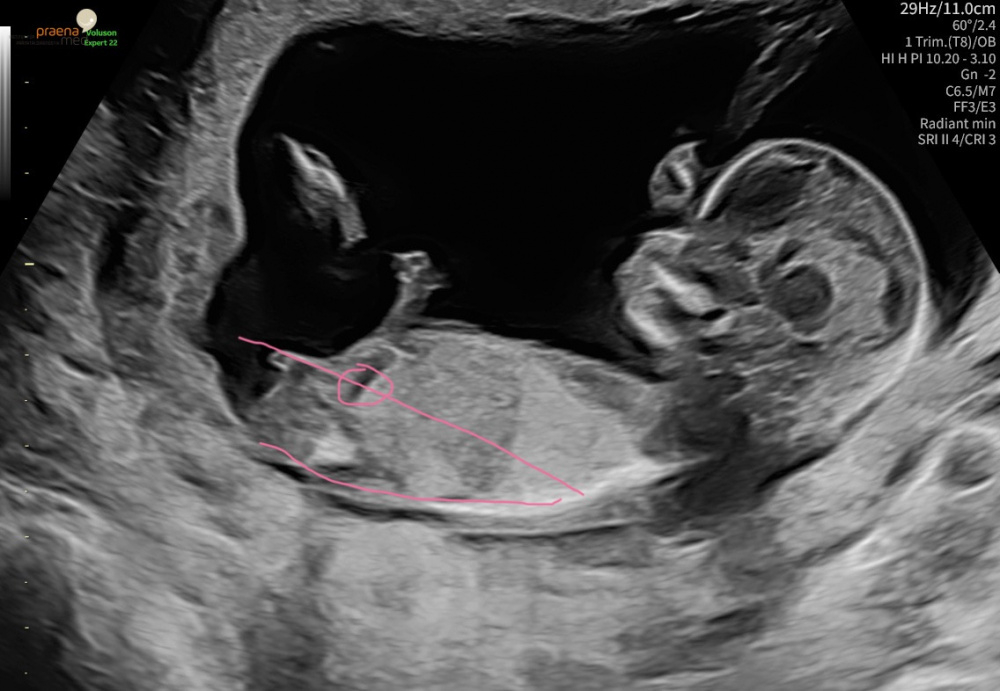

Ich war hier 12+2 der Frauenarzt wollte nichts zum Geschlecht sagen aber ich tendiere eher zum Jungen oder sah es bei einem Mädchen auch so aus in der 13ten Woche?

Nun war ich letzten Montag beim Ersttrimesterscreening. Da war ich 13+1. Die Ärztin meinte am Schluss sie hätte etwas gesehen. Ein Zipfel, ziemlich schmal und spitz. Bei meinem Sohn sah das ganz anders aus. Dennoch sagte sie Tendenz Junge. Ich weiß man soll sich über ein gesundes Kind freuen. Ich weiß dass ich das Kind liebe auch wenn es wieder ein Junge wird. Aber ich bin so traurig und kann seit dem an nichts anderes denken. Nun habe ich viel gelesen und auch hier immer wieder gehört, dass sich Ärzte irren, dass dieser Zipfel auch bei Mädchen vorkommt, usw. Wir haben auch den nipt gemacht. Da steht das Geschlecht aber nicht drin weil das Ergebnis zu früh war(muss ja mindestens Ende ssw 14 sein). Das heißt ganz sicher weiß ich es immer noch nicht und wollte nun mal eure erfahrenen Augen drauf schauen lassen... Was seht ihr auf den Bildern? Das eine ist von 6+1,die anderen vom Screening letzte Woche. Was ist eure Einschätzung? Kann mir jemand Hoffnung machen, dass die Tendenz falsch ist? Hatte jemand schon mal eine falsche Tendenz in der Woche? Bitte helft mir!